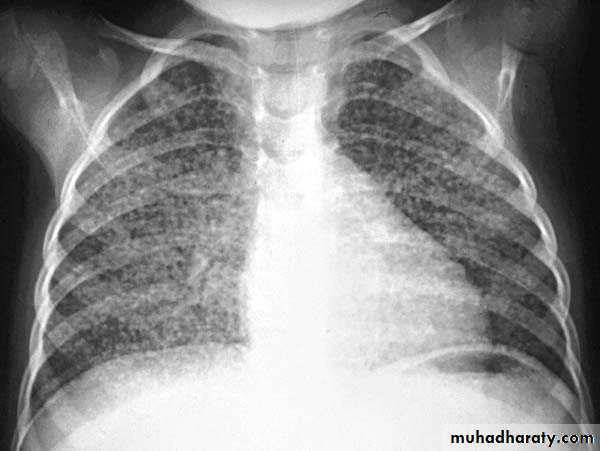

Post primary TB broncho pneumonia cotton wool signBilateral patchy opacities of the upper lobes of the lungs, cotton wool sign.

61.post primary TB notice upper apical Broncho pneumonic shadow

Bilateral Patchy opacification of the lungs involving upper zones, a cavity can be seen in the right uper lobe( 3rd photo)bronchopnemonia

Bilateral patchy opacity mainly involving lower lung zonesprimary TB bronchopnemonia

Bilateral patchy opacity mainly involving upper lung zonesBoth of them have similar appearance of broncho pneumonic shadow